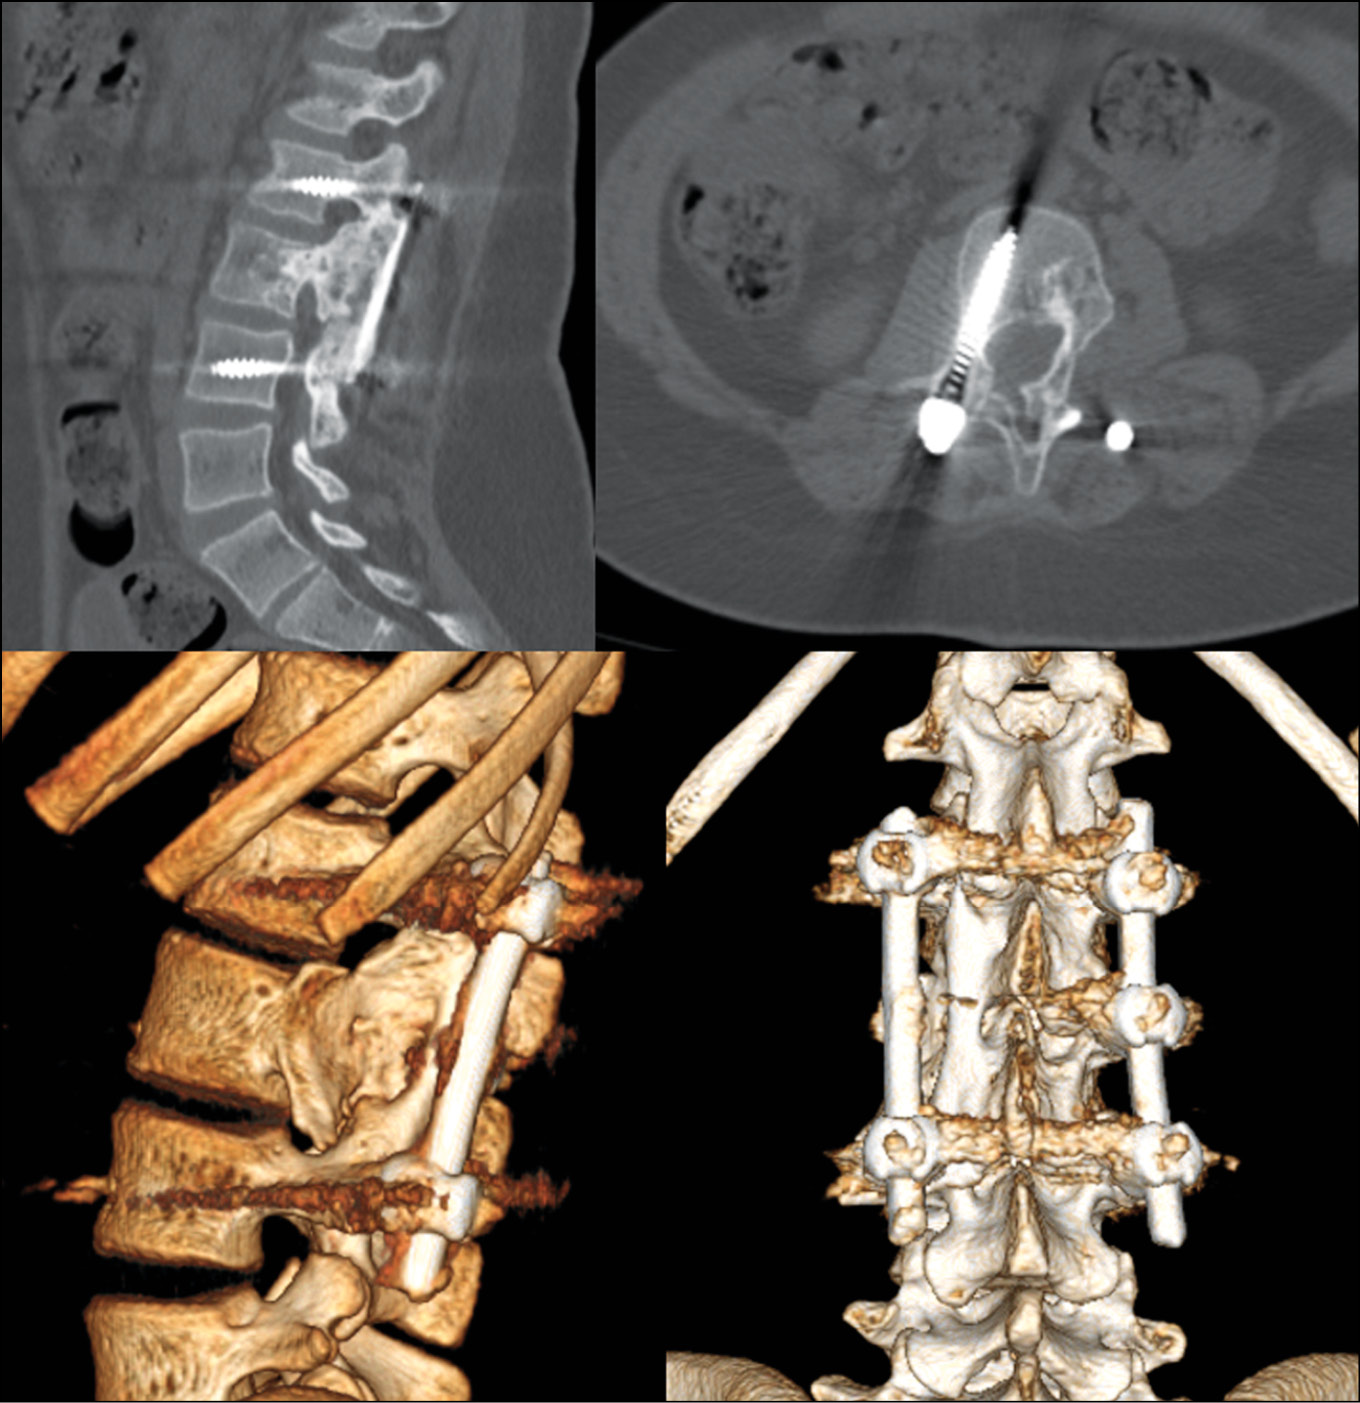

Пациентка вертикализирована на 3 сутки в ортопедическом ортезе с фиксацией поясничного отдела позвоночника. Болевой синдром полностью купирован на 5 сутки. При динаммческом наблюдении в течении 1,5 лет (рис. 6). Признаков рецидива не выявлено. Костный блок сформировался на 9 месяц с момента операции. При КТ исследовании отмечена стабильность металлофиксации, отсутствие признаков рецидива патологического процесса, интеграция в костный блок аллотрансплантата, а так же восстановление костной ткани по типу «памяти формы».

Рис. 6. КТ зоны операции через 1,5 лет с момента хирургического вмешательства

Fig. 6. CT scan of the operation area in 1.5 years after surgery

Учитывая возраст пациентки и отсутствие выраженного продолженного роста позвоночного столба (Risser 4) показаний к удалению металлоконструкции на момент последнего наблюдения не выявлено.